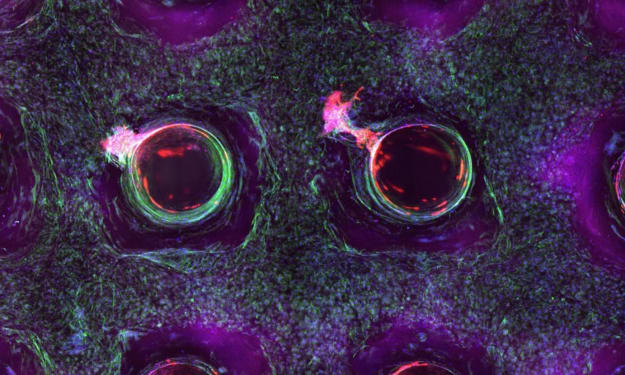

Do our skin have these ???

Title: The Integumentary System: Unveiling the Marvels of Skin, Hair, and Nails Introduction Step into any store, and you'll encounter a vast array of soaps, lotions, conditioners, and polishes dedicated to grooming our skin, hair, and nails. While some view these products as mere vanities, they are, in fact, the tools that care for, maintain, and decorate our integumentary system. Beyond their cosmetic applications, these resilient tissues serve a multitude of functions, many of which go unnoticed. However, when we do notice the workings of our integumentary system, it is often due to uncomfortable or unsightly conditions. This article aims to shed light on the vital functions of our integumentary system, emphasizing the importance of its care and maintenance for overall health.

What about SKIN ?

Title: The Remarkable Complexity of Your Skin: A Closer Look at the Body's Largest Organ Introduction When we think of organs, we often imagine the heart, liver, or lungs. However, we tend to overlook the largest organ of all—our skin. Beyond its external appearance, the skin serves crucial functions, such as protection, temperature regulation, fluid balance, and even vitamin D synthesis. Composed of three layers—the epidermis, dermis, and hypodermis—each with its own unique set of cells, the skin is a remarkable organ that deserves recognition and understanding.